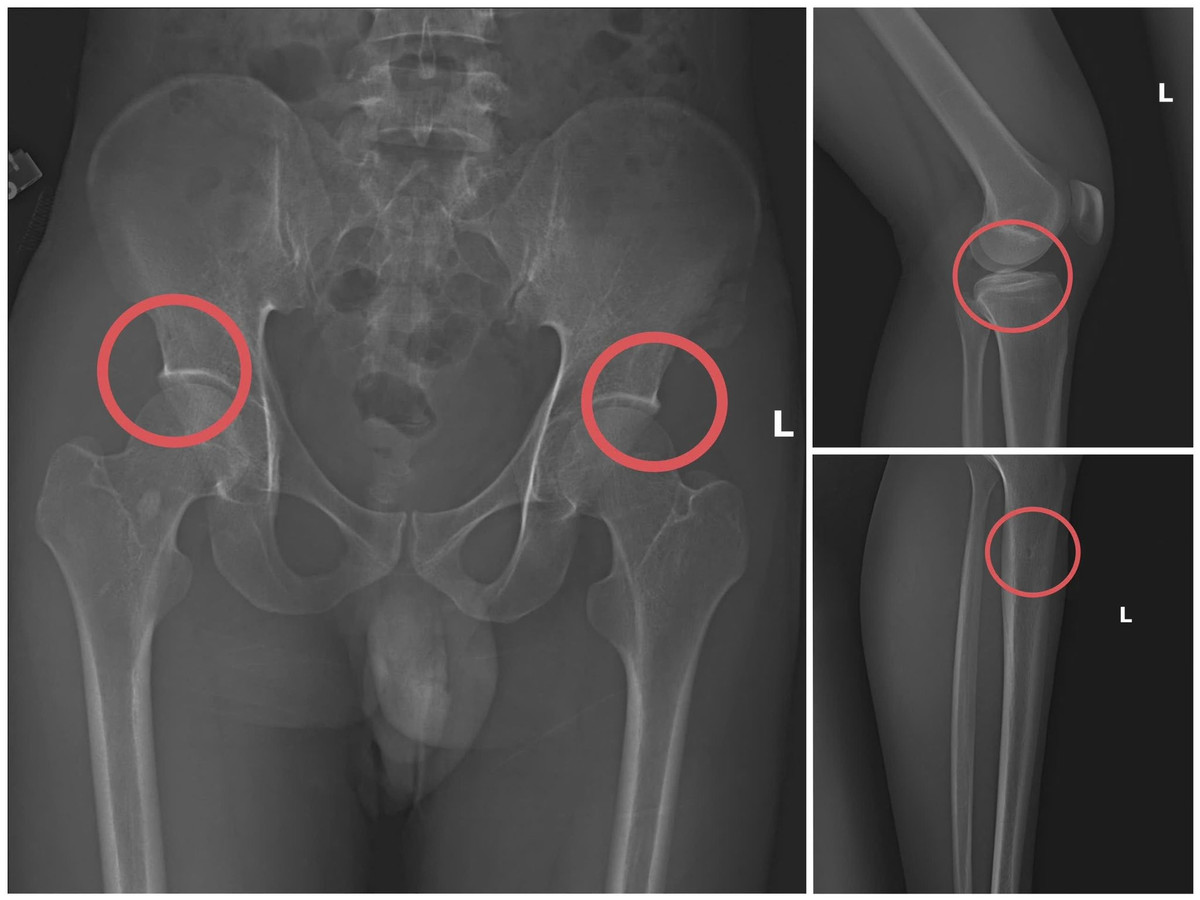

433.jpg

Bản phim chụp XQ một số tổn thương xương do đối tượng tạo ra

Châu từng có thời gian dài công tác trong ngành y, am hiểu sâu cấu tạo xương khớp và cơ chế chi trả bảo hiểm các thương tích gãy xương giá trị cao. Do đó, đối tượng này đã dựng lên một quy trình trục lợi bài bản, từ vận động mua bảo hiểm, tổ chức gây thương tích, hợp thức hóa hồ sơ bệnh án để chiếm đoạt tiền các công ty bảo hiểm.

Điều tra xác định, Châu trực tiếp tiêm thuốc mê rồi dùng kim tiêm, búa, đinh tác động vào xương người mua bảo hiểm, tạo nên các vết nứt, vỡ xương tương tự tai nạn thật. Khi tạo xong thương tích, Châu hướng dẫn các đối tượng dựng hiện trường giả như điện giật ngã, trượt chân ngã suối, nhằm hợp thức hóa bệnh án, hoàn thiện hồ sơ yêu cầu chi trả.